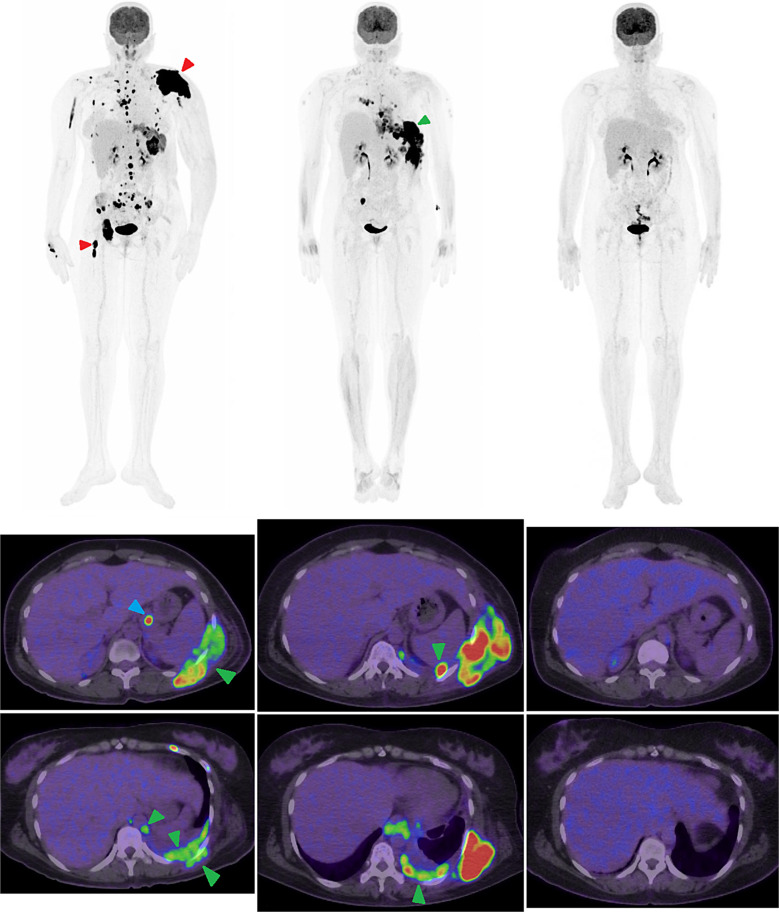

Case presentation: A 42-year-old Asian female presented with left shoulder pain and swelling, leading to the diagnosis of IgG lambda MM with extensive extramedullary disease. After initial partial response to D-VRD therapy, she developed MPE with complete left lung collapse. Following failure of second-line KPD-PACE therapy, she received teclistamab, achieving complete metabolic and morphological response documented by PET-CT. After maintaining remission for 10 months, she experienced relapse with pericardial involvement presenting as cardiac tamponade.

Conclusion: The patient demonstrated an unprecedented response to BCMA-targeted therapy with teclistamab, achieving complete remission that lasted 10 months - more than doubling the historical median survival of 4 months for MPE. Flow cytometry proved instrumental in rapid diagnosis, showing 11% lambda monotypic plasma cells in the pleural fluid. The subsequent pericardial involvement after initial complete response highlighted the persistent challenges in managing extramedullary disease. This case represents the first documented instance of sequential MPE and pericardial involvement in MM, demonstrating the potential of novel targeted therapies, particularly BCMA-directed approaches, in extending survival and improving outcomes in these rare but aggressive disease manifestations.